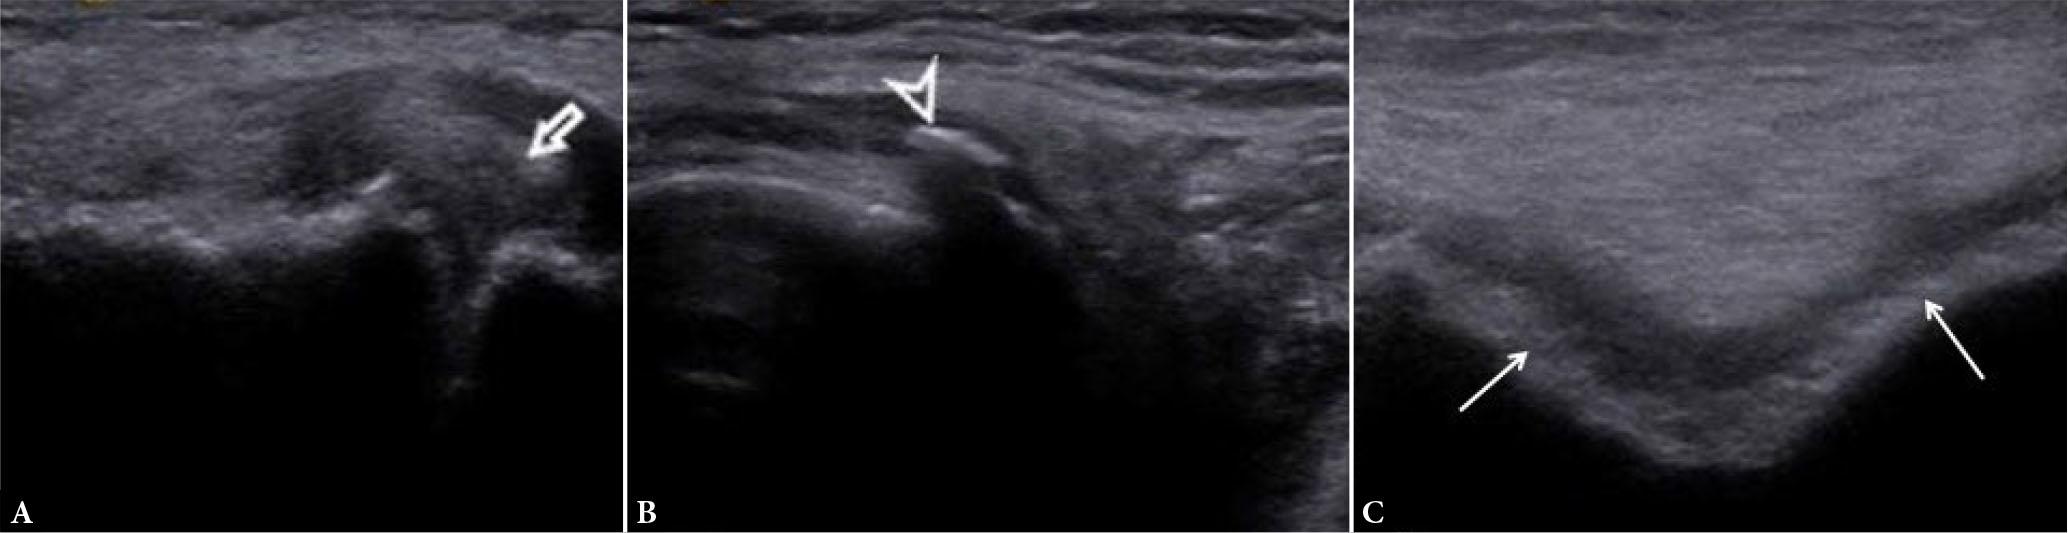

Fig. 22.

Osteoarthritis (OA). Long-axis US images of the knee joint show meniscal extrusion (arrow in A), osteophyte (arrowhead in B), and cartilage damage of trochlea (arrows in C), cartilage appears heterogeneous, with uneven thickness and fuzzy contours